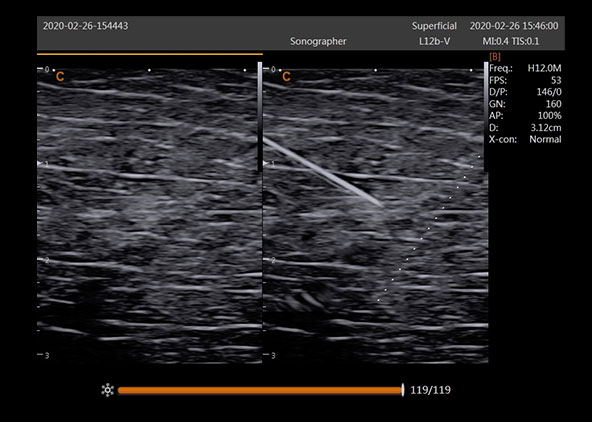

Super Needle

Enhance the needle displaying in image, without distortion of the needle. Decrease the complicated rate, increase the successful rate.